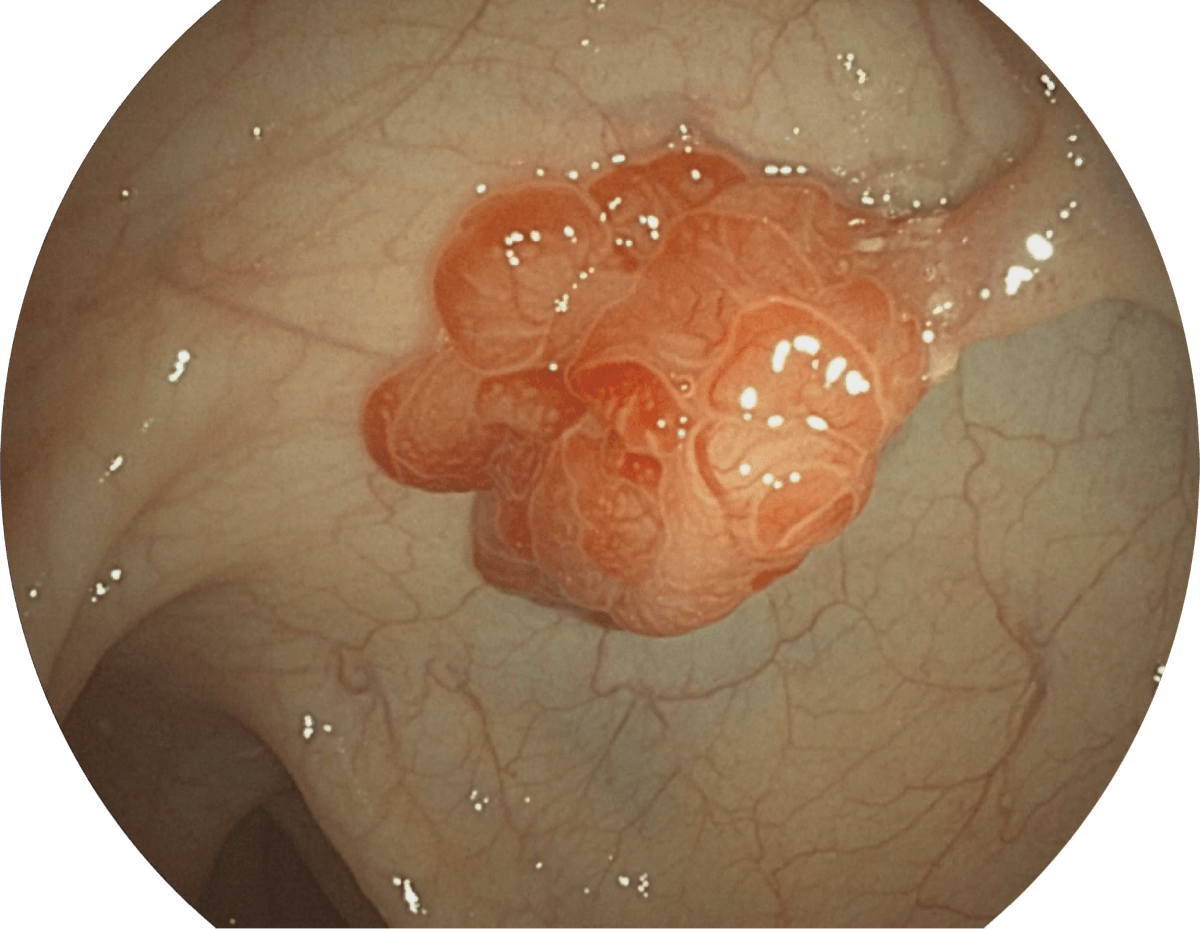

• WL

• SFI

• VIST

图像具有高亮度、高黏膜血管颜色对比度的特点,且不改变粘液、食物残渣、粪便的基本颜色,可在中远景下进行观察,助力消化道早期疾病的诊断。

强调浅层黏膜结构的同时,保证照明亮度和提升浅层微血管与中层血管颜色对比度,病变边界更清晰。